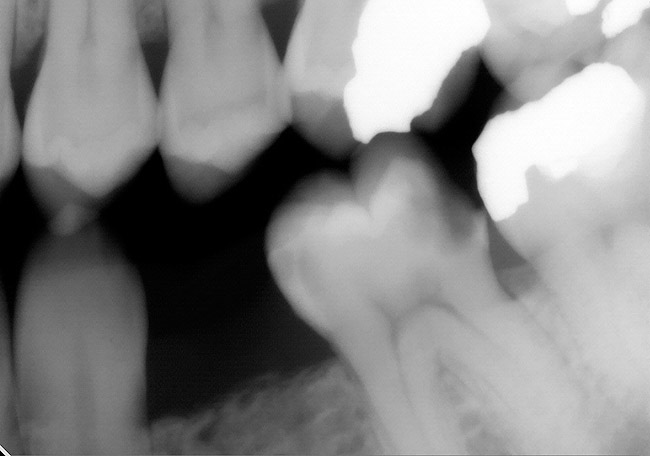

Figure 6A Bitewing radiograph. Deep caries evident radiographically for the mandibular first molar.

Figure 6A

Figure 6B Periapical radiograph. Deep caries evident radiographically for the mandibular first molar.

Figure 6B

The use of EPT to assess a tooth prior to restorative or endodontic treatment depends on the clinical situation. For teeth with obvious periapical radiolucencies indicative of chronic abscess or cysts, a pulpal vitality test will confirm the diagnosis (Figure 5). In the presence of deep caries, using an EPT can confirm pulp vitality before initiating the restorative procedure (Figure 6 and Figure 7). In the case in which the radiograph demonstrates significant caries near the pulp, the EPT can provide additional information. For this patient with no history of pain in the maxillary first molar, the radiographic and clinical appearance of occlusal caries lead to the use of EPT to demonstrate lack of pulpal vitality (Figure 8). For large Class V carious lesions, the radiograph is usually not helpful in determining potential endodontic needs. Using an EPT provides a more definitive expectation of the extent of the caries relative to the pulp (Figure 9).